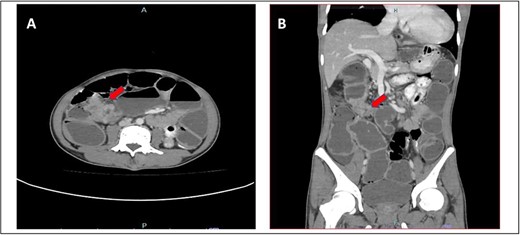

A 52-year-old Malay man, an active smoker, with underlying pulmonary hypertension secondary to atrial septal defect secundum with Eisenmenger syndrome and chronic lung disease. He had been experiencing symptoms of intestinal obstruction for a week. He had abdominal pain for 1 day, vomiting for 2 days, and unable to pass motion for the past 1 week. Patient was tachypnoeic with a respiratory rate of 35/min, a pulse rate of 116 bpm, and SPO2 of 90% under high-flow nasal cannula 50%/50 L. Abdominal radiograph showed dilated large bowel. Computed tomography abdomen and pelvis revealed short segment circumferential enhancing bowel wall thickening at rectosigmoid region causing intraluminal obstruction and presence of target sign at left lumbar region suggestive of jejunojejunal intussusception (Figs 2 and 3).

(A) Axial view and (B) sagittal view of computed tomography showed short segment circumferential enhancing bowel wall thickening at rectosigmoid region causing intraluminal obstruction (red arrow).